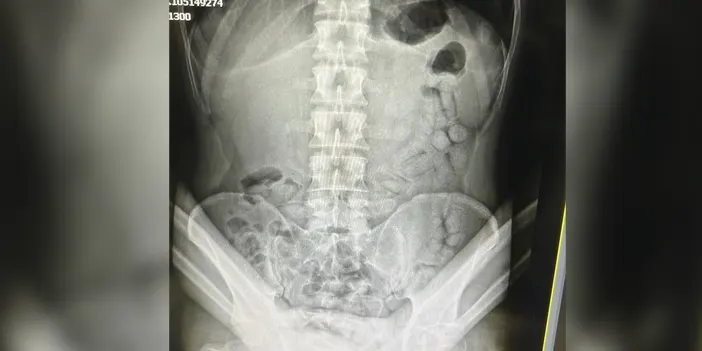

Adli makamların talimatı üzerine Gümüşhane Devlet Hastanesi'ne götürülen şüpheliye iç beden muayenesi yapıldı. Muayenede, bağırsaklarında 55 adet kapsül tespit edildi.

Hastanede yapılan müdahale sonucu çıkarılan kapsüllerin içinden toplam 317,46 gram metamfetamin ele geçirildi.